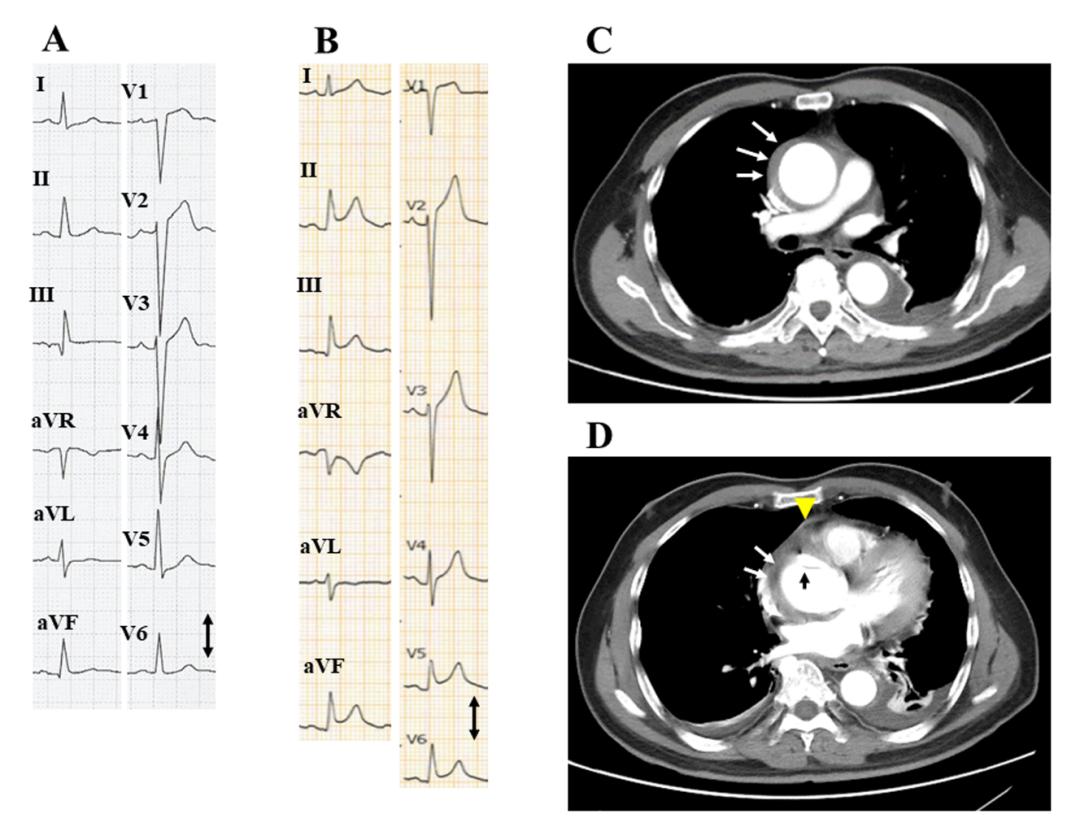

图1. 病例1的12导联心电图和对比增强CT扫描

A:入院前3天的心电图,QRS波群略微增宽(110 ms),V1-3导联深S波,轻度ST段抬高,提示左心室肥大,这些是慢性变化;

B:入院时心电图,弥漫性ST段抬高,PR压低(黑色箭头),符合急性心包炎表现,垂直箭头指示1 mV,纸张速度为25毫米/秒(图2、图3相同)

C、D:对比增强CT显示,局部内膜瓣(图D黑色箭头),升主动脉壁内血肿(白色箭头),少量心包积液(图D黄色箭头)。